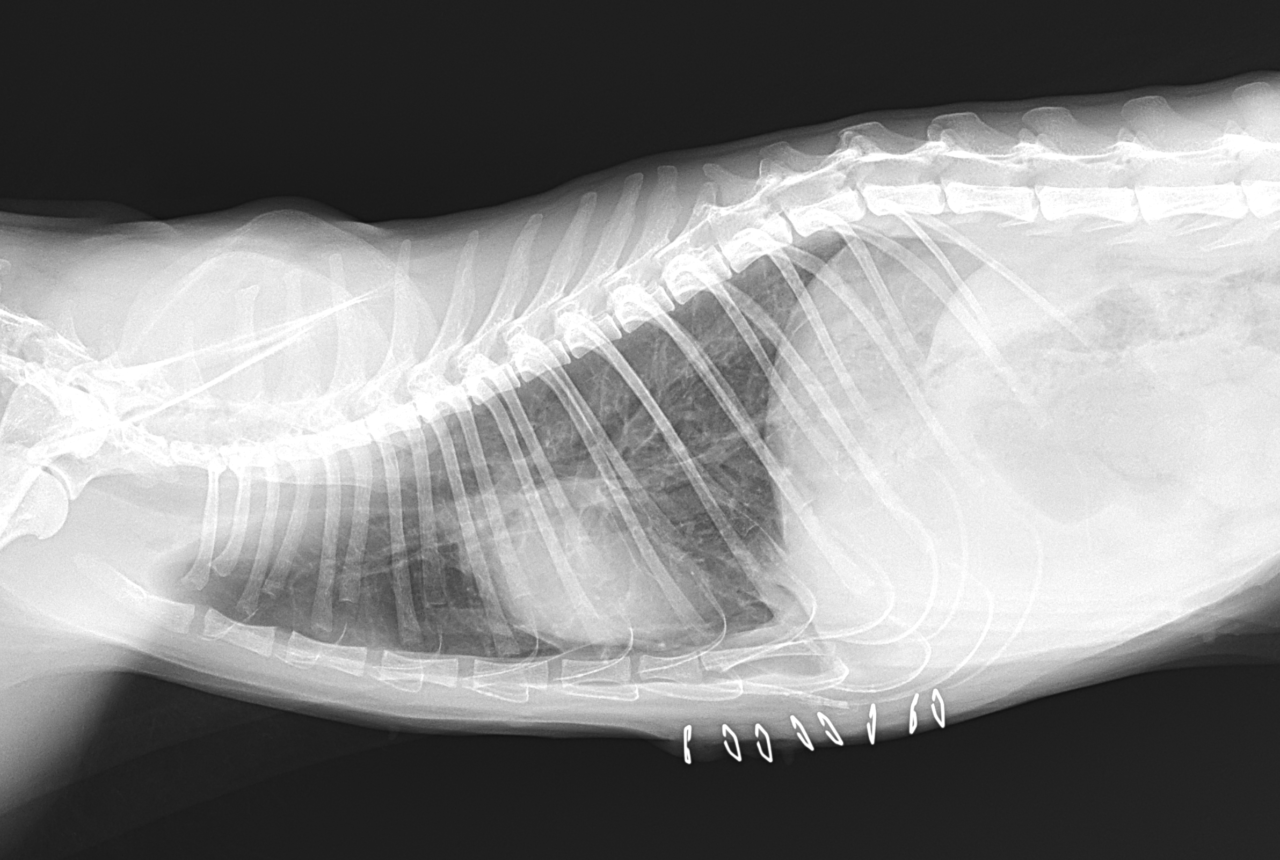

保護した猫さんの呼吸が早いかも??? かかりつけの先生に相談されたようです。エックス線検査で横隔膜ヘルニアが確定されました。外科的な対応を希望され来院されました。肝臓のほとんどが胸腔内にヘルニア(逸脱)しており、開腹アプローチで横隔膜を整復しました。正しい位置に臓器が戻ったので、これからは呼吸が楽になります。